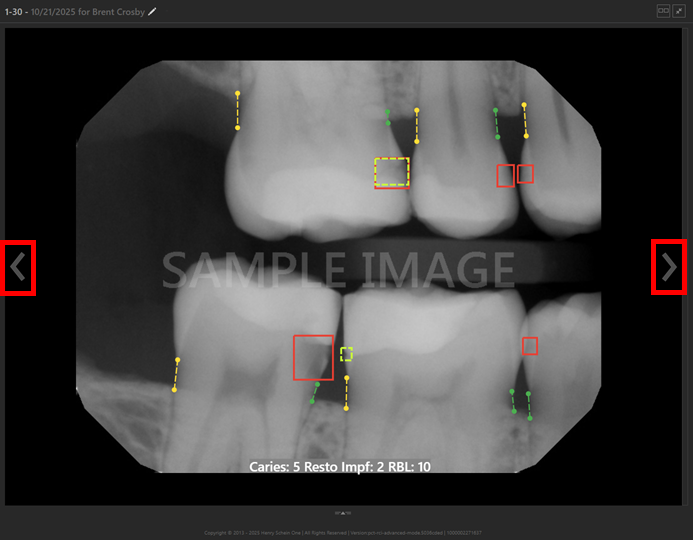

Videa AI Panel

If your location uses Dentrix Ascend Detect AI, an AI panel now appears automatically when you view an intraoral X-ray image. The panel displays a summary of the AI analysis performed on the displayed teeth (using all images, with those same teeth in common, that were acquired during that visit—in the same series).